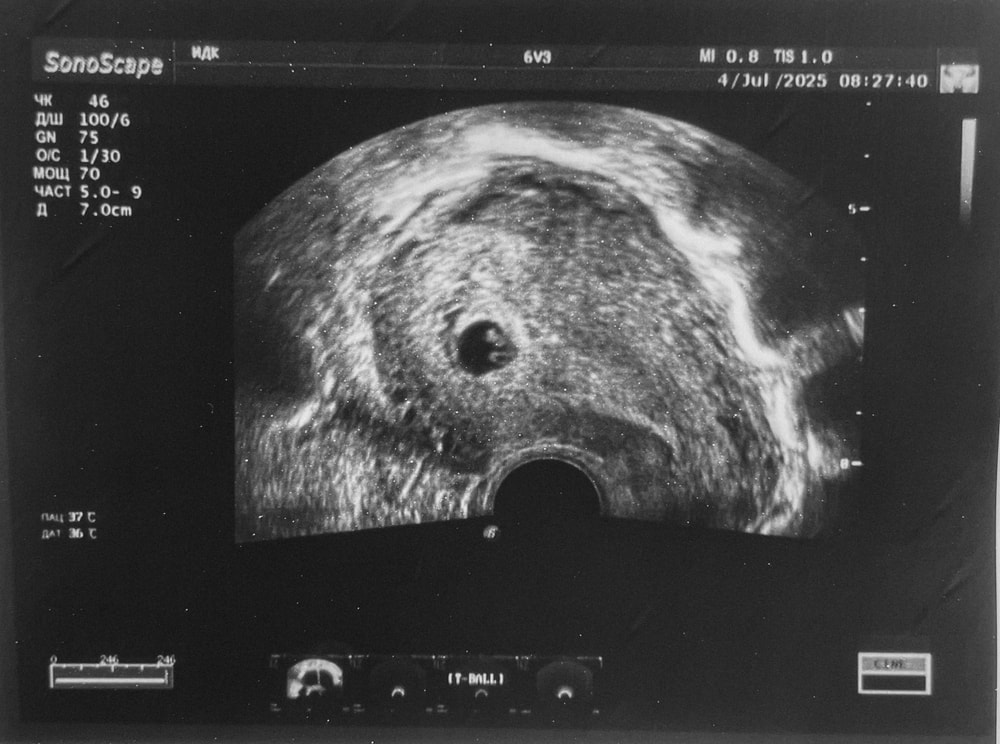

6 недель 3 дня 💕

Сегодня уже увидели эмбрион и сердцебиение 🙏🏼

ПЯ - 12,5 мм

ЖМ - 3,7 мм

КТР - 5,3 мм